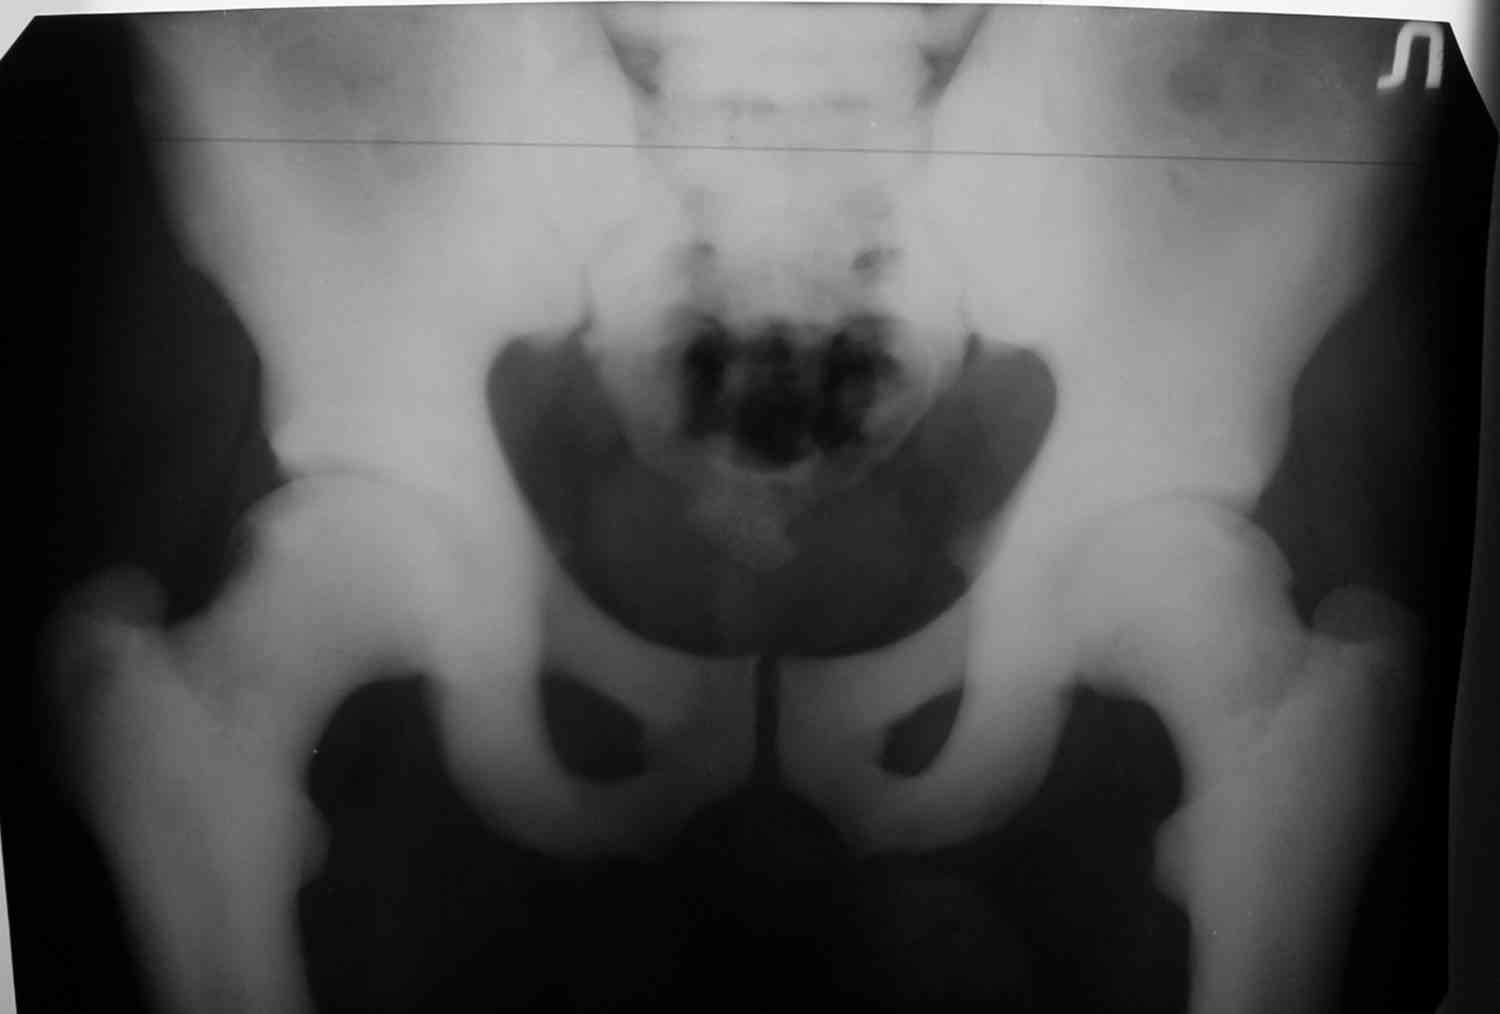

Уважаемый Константин Иванович! Полностью согласен с проф. Михайловым, данный случай не похож на мраморную болезнь, при которой имеется резкое, строго симметричное и генерализованное уплотнение костной ткани (остеопетроз), и кость оказывается построенной преимущественно из гомогенного компактного костного вещества. Для примера привожу случай из архива нашего института (бедренные, плечевые кости и таз, рис 1,2,3)